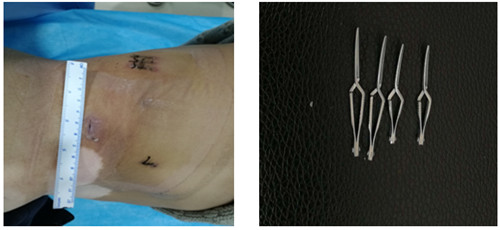

如圖一圖二為腫瘤位置及大小,圖三即為手術操作通道(5mm、10mm、12mm),術中游離出腎動脈后,用圖四的血管夾臨時阻斷腎臟血液供應,剜除腫瘤后,在腔鏡下縫合腎臟,確定縫合嚴密,再恢復腎臟血供!要求阻斷時間不能超過30分鐘,此例患者阻斷17分鐘!此類手術技術難度大,腹腔鏡下縫合要求高,并對血供阻斷有時間要求!